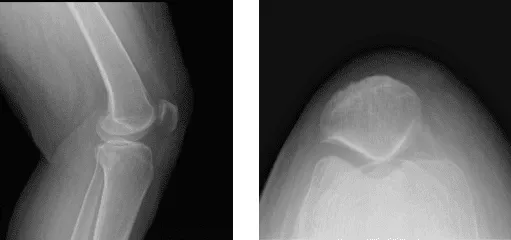

Los resultados de las radiografías presentados y revisados mostraron que no existen enfermedades degenerativas. Aconsejaron al paciente que se sometiera a una resonancia magnética y descubrí que hay edema subcutáneo tanto anterior como anteromedial.

Sospecha de desgarro en el cuerno posterior del menisco medial. Hay una señal oblicua muy tenue que parece extenderse hasta la superficie articular inferior. Se observó una ruptura parcial del LCP proximal y también se observaron condromalacia leve de rótula y bursitis infrapatelara profunda.

Radiografía de la rodilla izquierda completa con rótula